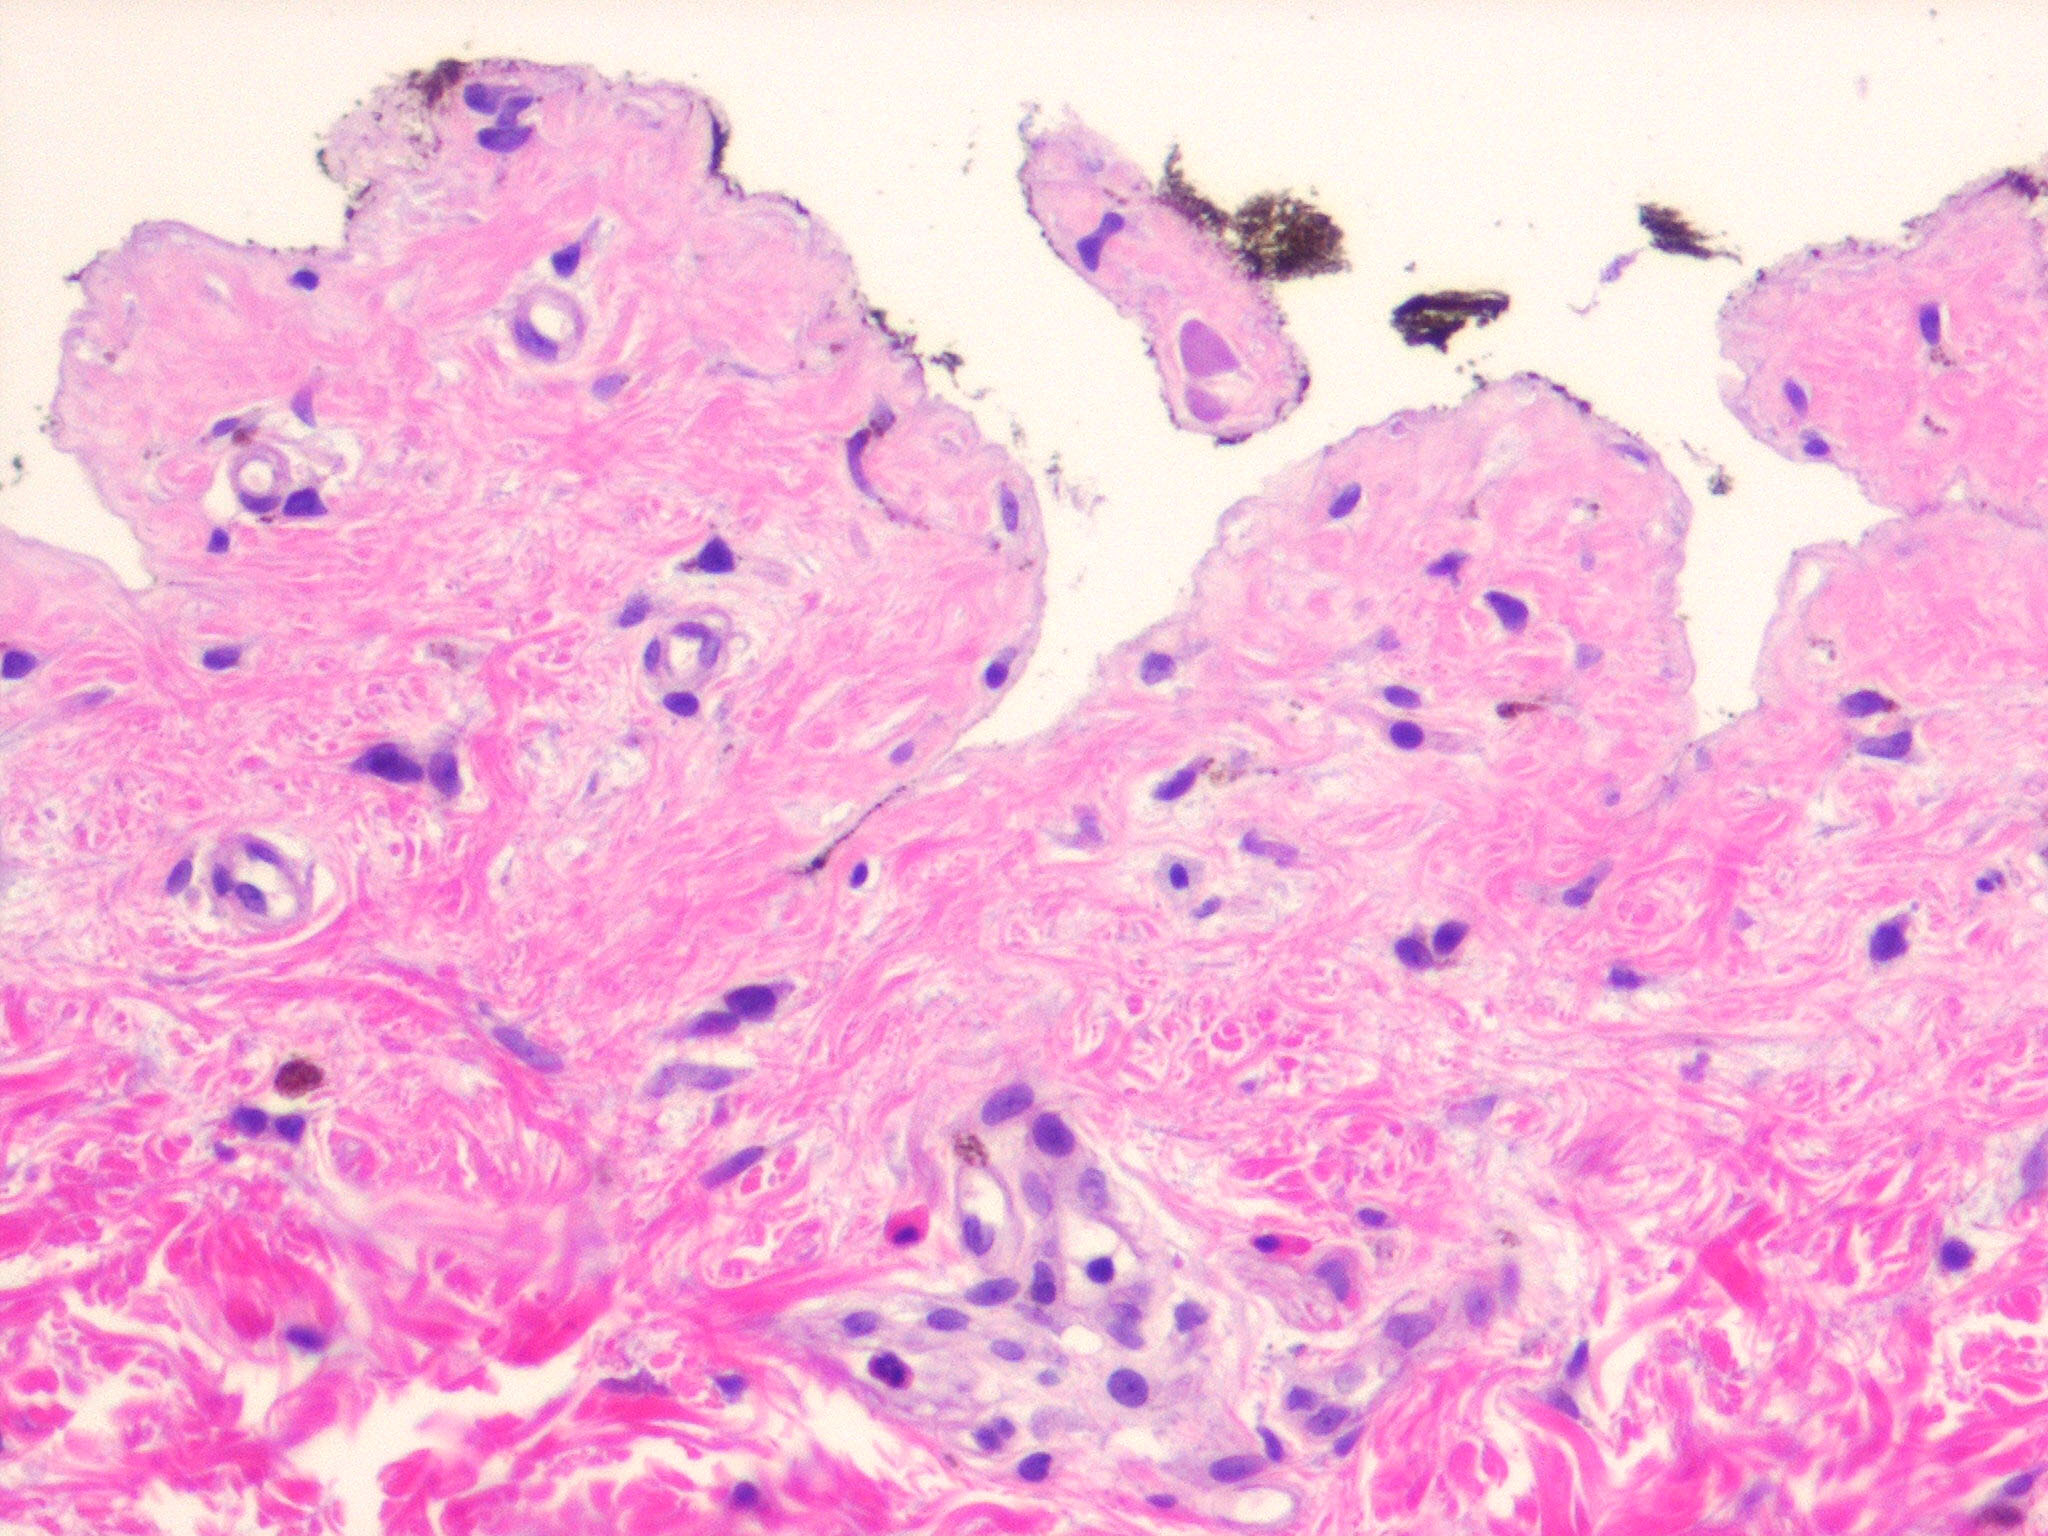

In early lesions, papillary dermal edema in combination with a cell-poor or cell-rich perivascular lymphocytic and eosinophilic infiltrate is present. The blister arises at the dermal-epidermal junction . In the cell-rich pattern, which correlates clinically with blisters arising on erythematous skin , eosinophilic papillary abscesses may develop with numerous perivascular and interstitial eosinophils intermingled with lymphocytes and neutrophils in the superficial and deep dermis. Early lesions may have the histologic features of eosinophilic cellulitis (Well’s syndrome). Eosinophilic spongiosis may occur. The cell-poor pattem is observed

when blisters develop on relatively normal skin , in which there is usually a scant perivascular lymphocytic infiltrate with few eosinophils, some scattered throughout the dermis and others near the epidermis. The blister contains few inflammatory cells. Epithelial migration and regeneration may result in an intraepidermal split in older blisters. Similar to pemphigus vegetans, a hyperplasia of the epidermis, subepidermal bullae, and accumulations of eosinophils and lymphocytes may be seen.